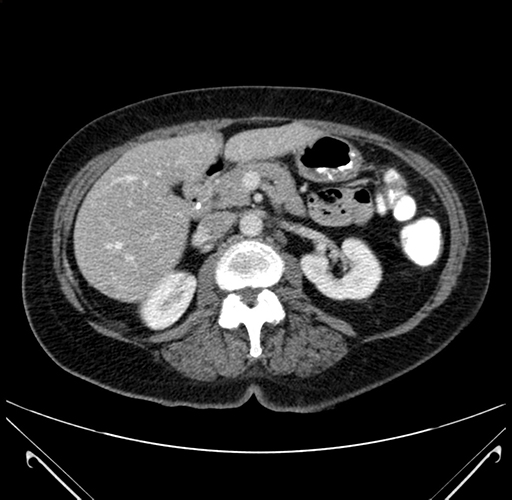

Imaging Analysis

Look through the patient's CT scan to identify any areas of concern for the necessary procedure.

Pre-Chemo: Axial Venous

Based on your CT findings, which issue(s) would give reason for "planned slowing down moment(s)" in this case?

Considering a standard right hepatectomy procedure, what step(s) of the operation would you do differently in this case?